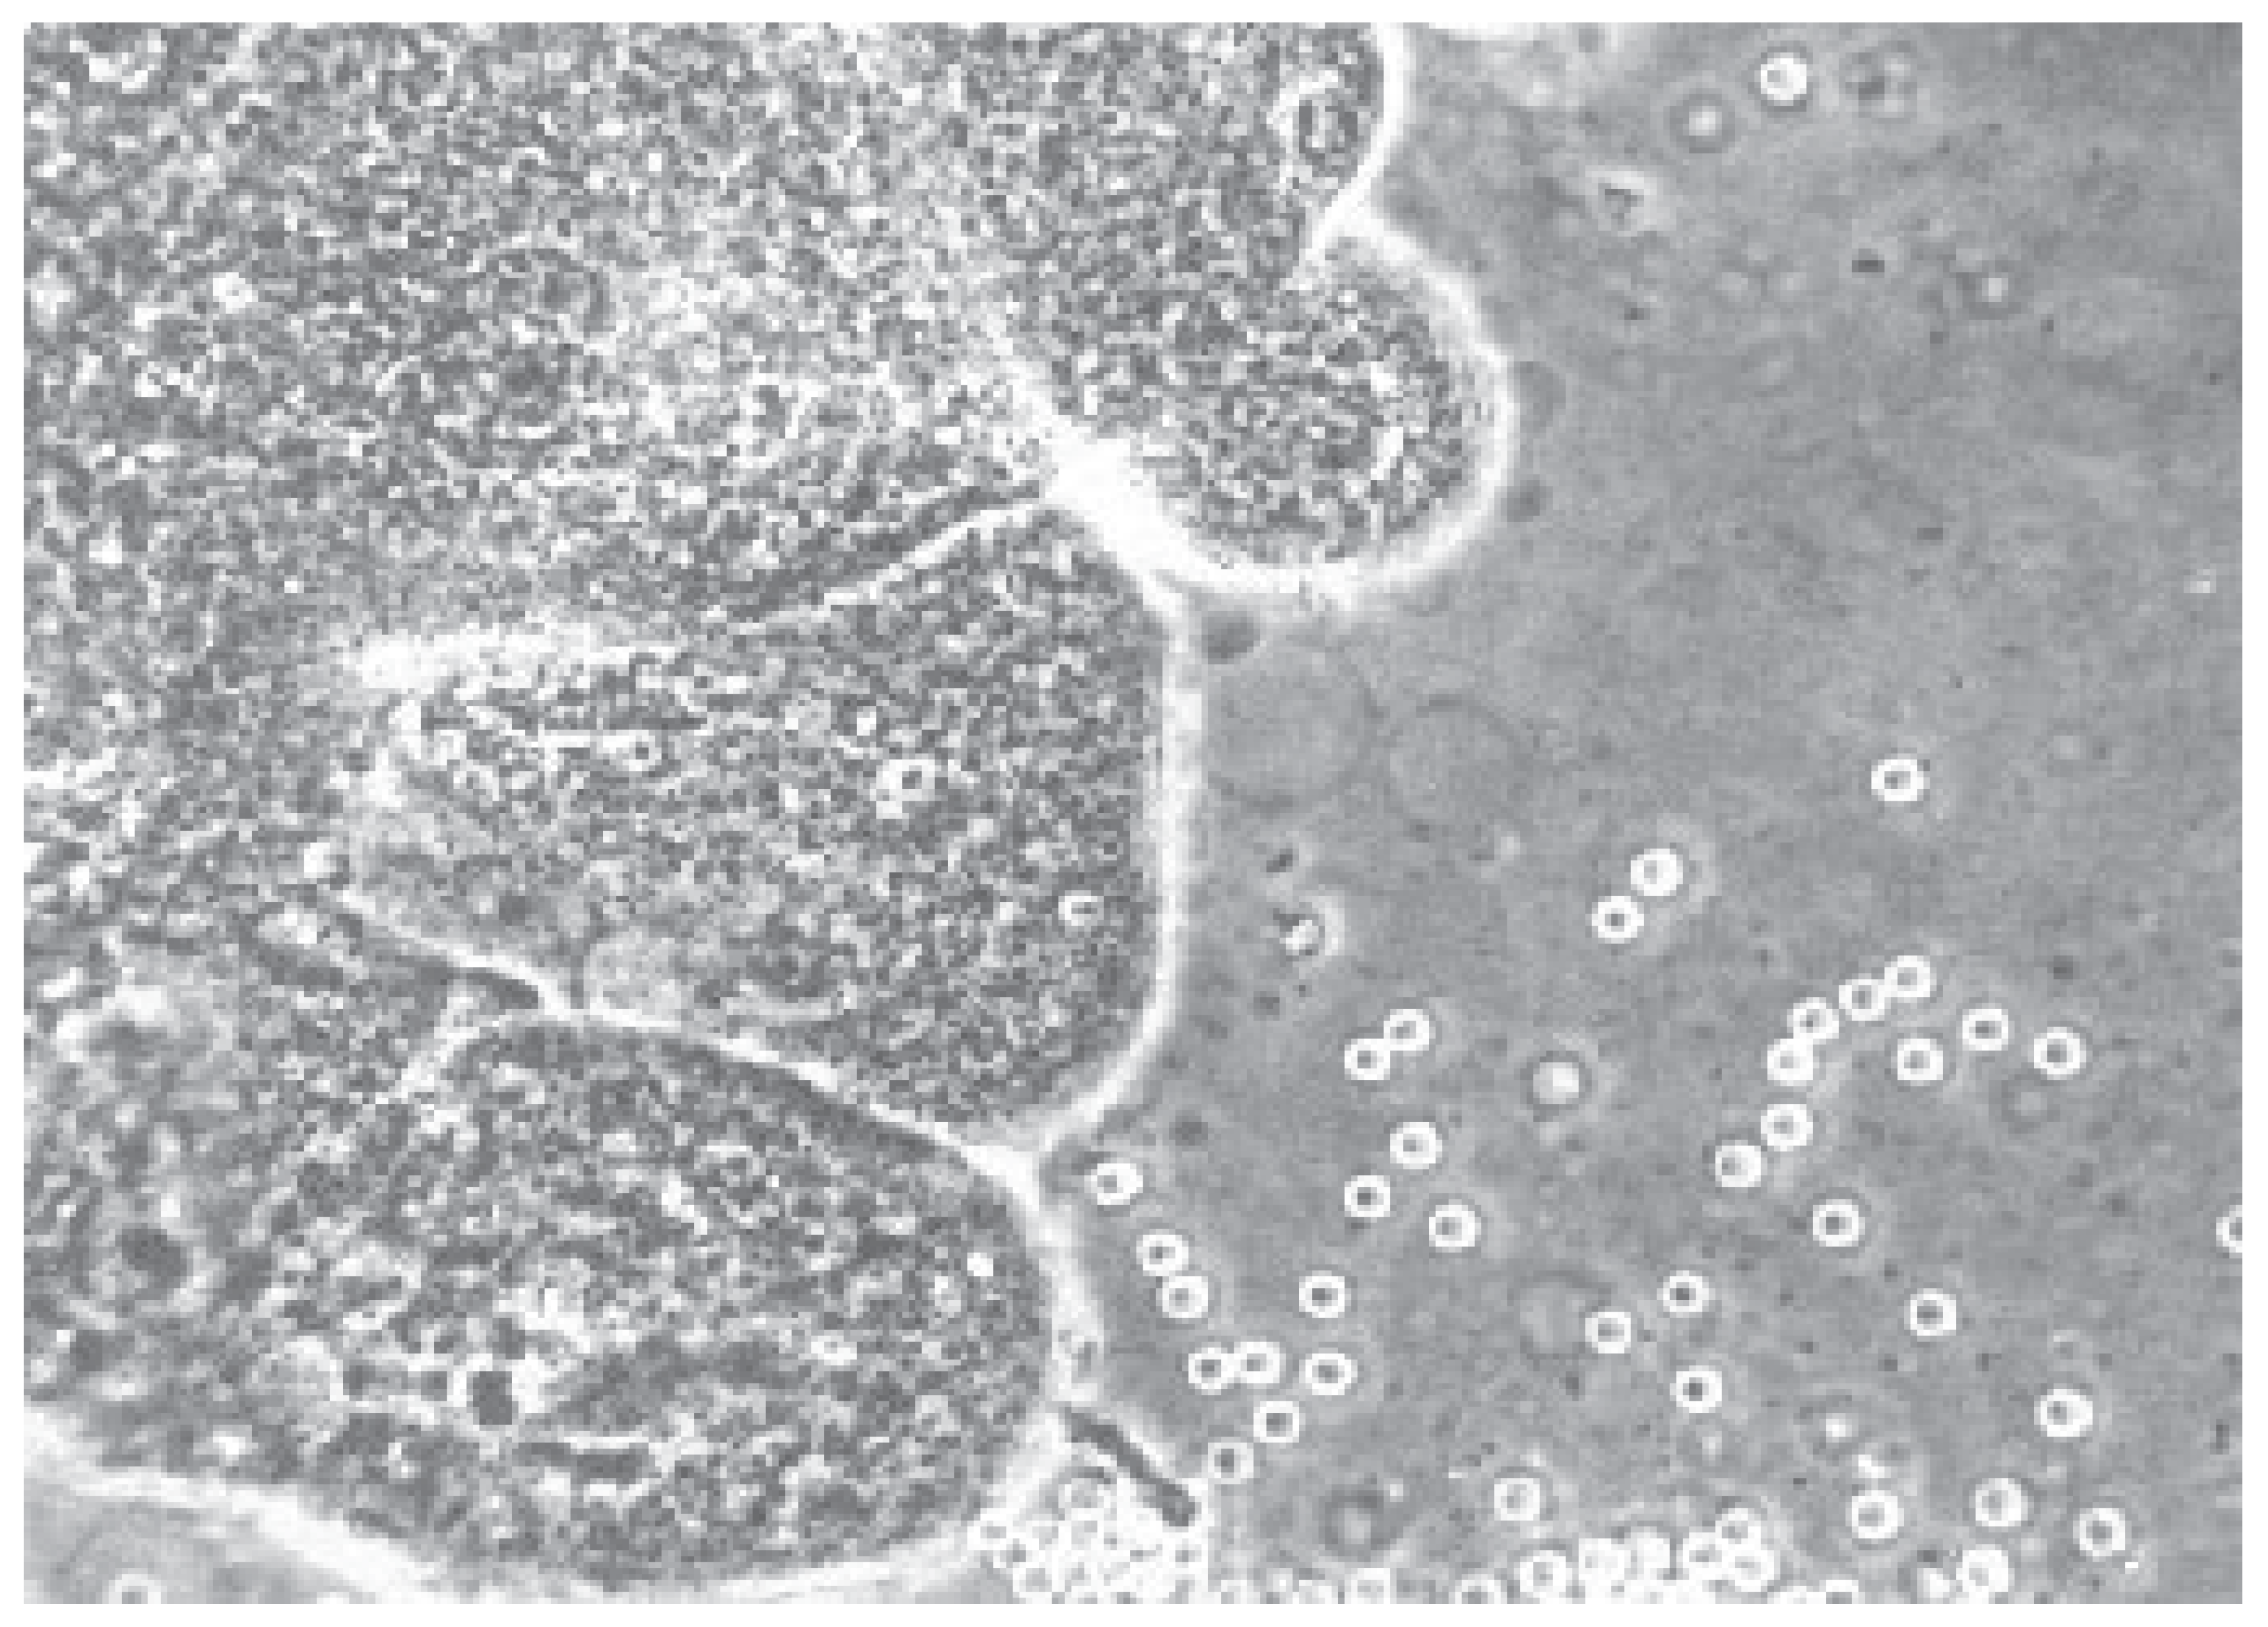

Transcervical chorionic villus sampling (TC-CVS) was performed with the patient in the lithotomy position. Aspirations were performed at 10 to 13,6 weeks of gestation age. To perform the aspiration, we used a 26 cm long Portex catheter or a 24 cm long Holzgreve-Angiomed catheter, with continuous real-time ultrasonographic guidance provided using a Voluson 8 or 10 scanner, with a 5-9 MHz transducer. The catheter was inserted through the cervix into the chorion frondosum, rotating the catheter to aspirate the tissue into a 20 ml plastic syringe containing 5 ml culture medium. Amounts of 1 to 25 mg of chorion frondosum tissues were obtained and the modified short term-culture (overnight), with modification, was used in all cases for caryotipization [19,20,21,22,24,25,26,27,29,33,34,35,36]. On the other hand, transabdominal chorionic villus sampling (TA-CVS) was performed with the patient in the supine position, useding single a 20 gauge-90 mm spinal needle. Upon disinfecting the anterior abdominal wall and the patients Havin an empty urinary bladder, the needle was inserted under ultrasound guidance, into the middle of the chorion frondosum, where the angle of insertion was slowly and the angle was changed by 20 to 40 degrees in the presence of negative pressure chorion frondosum tissue was aspirated into a 20 ml syringe, containing the medium previously specified. Further transvaginal chorionic villus sampling (TV-CVS) was performed with the patient in the lithotomy position. To perform aspiration, we used a 35 cm long 20-gauge needle with continuous real-time ultrasonic guidance provided with a 5-9 MHz vaginal transducer with a guide needle. The needle was inserted through the fornix (anterior or posterior) into chorion frondosum (Figure 1 a and Figure 1 b) and the tissue was aspirated into a 20 ml syringe, by combining repeated strong suction and slow backward and forward movement of the needle tip. After two failed passes, for all three techniques, the women were offered another CVS session a week later. All 5500 early CVS sampling was performed by a single operator: M.P.

Figure 1. a. i 1 b. Transvaginal aspiration of CVS (TV-CVS) at the gestation weeks of 11 weeks. The route to biopsy is longer than with TA-CVS.